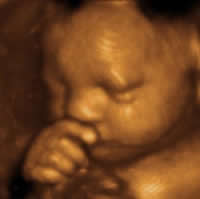

Difference between 3D Ultrasound and 4D Ultrasound

Key difference: 3D ultrasounds create a three-dimensional image of the fetus. 4D ultrasounds capture the motion of the fetus as well as a three-dimensional image.

include("ad3rd.php"); ?>3D ultrasound bounces sound waves off the fetus from various different angles, and produces a three-dimensional image of the fetus. This image shows depth and great detail. A 4D ultrasound uses the same technology as 3D, but also shows movement. 4D takes three to four images per second, which compiled together show movement. It can show the unborn baby moving around, yawning, sucking his or her thumb and even appearing to “wave”.

Usually, a 2D ultrasound is enough to serve the purpose of routine check-up, but sometimes a 3D or 4D is needed to confirm an abnormality. 4D makes it possible to assess fetal development and/or diagnose issues more efficiently, as the doctor can see the organs in real-time. However, the popularity of 3D and 4D comes mainly from the fact that 3D provides high-definition color pictures of the unborn child, which the parents can take home and that 4D ultrasounds showing the unborn child’s movement can be saved to a DVD as keepsakes and for later viewing.